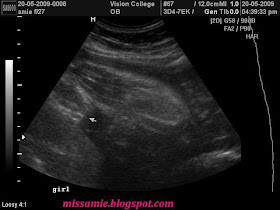

4. All 5 rompers from Gap.. ada 2 my sis beli during her holiday at bandung last February.. Tadaaa..what's ur comment? All the rompers mcm baby boy punya kan? kan? Hahaha... I tak tahu.. masa I amik, my insticnt slalu ckp, take the blue one! Sbb tue till now, ini jer yg I dah beli... Lain2, kita tggu je nanti yer.. Tomorrow will be my next scan.. Kalau tak nampak jugak, I pasrah. Hihihi...